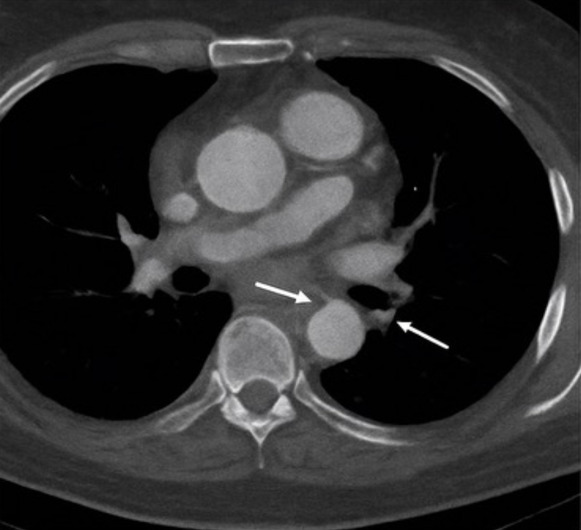

Emergent computed tomography angiography (CTA) revealed a Stanford type A aortic dissection originating in the ascending aorta and extending into the proximal descending thoracic aorta (Figure 2). The true lumen was patent, and no pericardial effusion was identified (Figure 3). The maximal diameter of the ascending aorta measured 6.2 cm. The dissection involved the aortic root and partially extended into the arch, while the innominate and left common carotid arteries remained patent. Transthoracic echocardiography revealed mild aortic regurgitation with preserved left ventricular ejection fraction (55%) and no pericardial effusion.